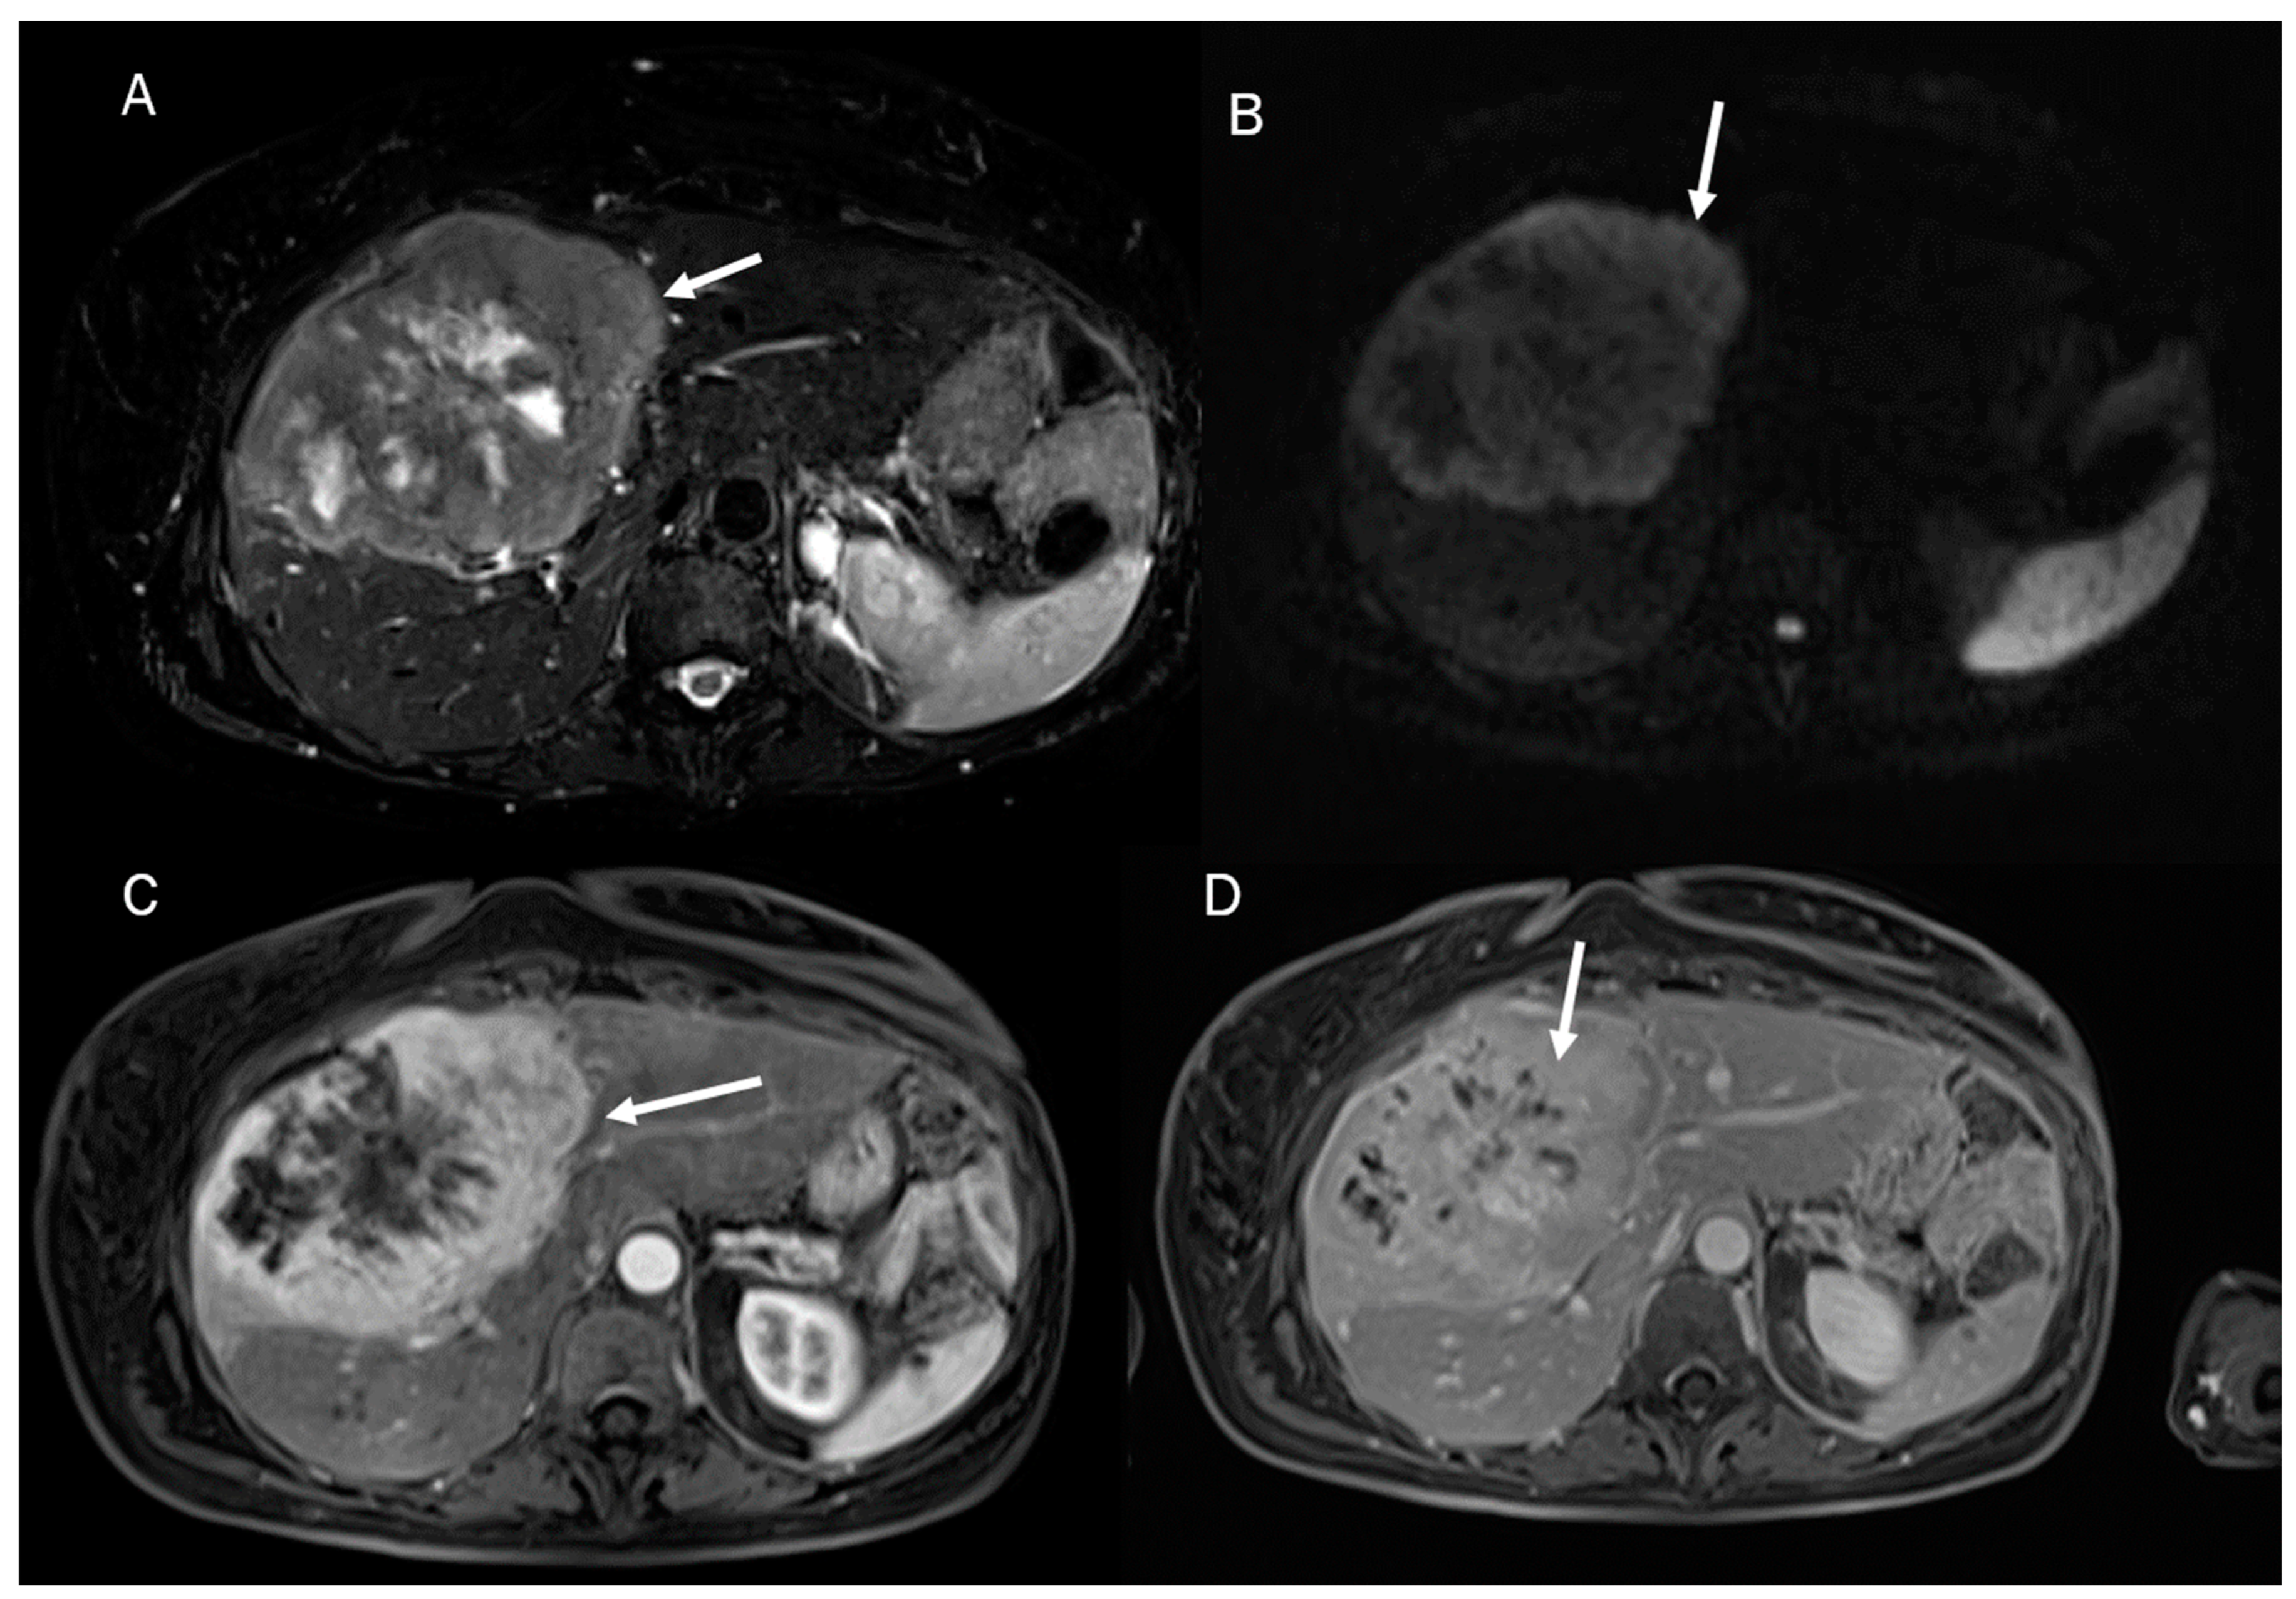

Despite the challenging nature of this task, conducting a differential diagnosis between ICC and other liver lesions, especially concerning HCC and combined hepatocellular cholangiocarcinoma (Figure 1), is mandatory to conduct appropriate treatment planning [9,10]. To help radiologists and clinicians, several authors have proposed radiomics models to better define tumor characteristics and disease progression [11,12].

Figure 1.

Combined hepatocellular cholangiocarcinoma MRI assessment: the lesion (arrow) shown in T2-W sequence (A); targetoid appearance, with restricted diffusion in b800 s/mm2 (B); and progressive contrast enhancement during contrast study (arterial phase (C) and portal phase (D)).